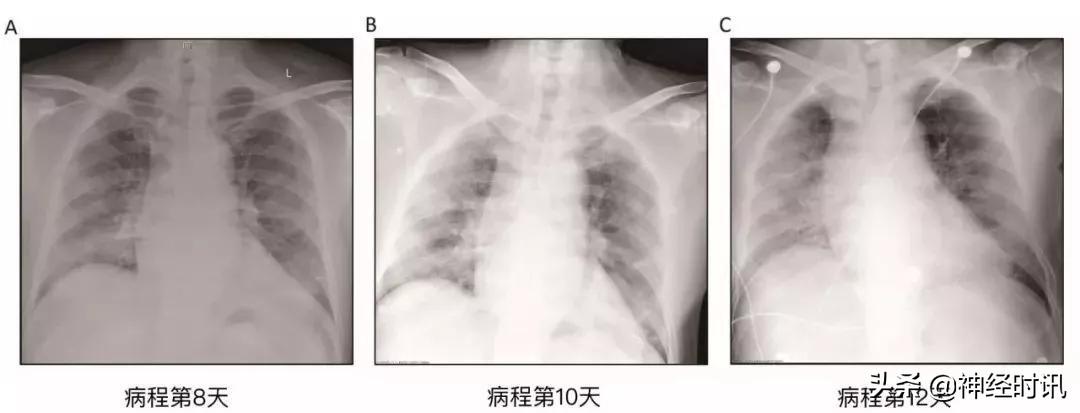

起病第12日,胸片显示患者双肺进行性浸润影和广泛网格状密度增高影。由于患者有幽闭恐惧症,他多次拒绝ICU的呼吸机支持,只好对其进行高流量鼻导管吸氧(HFNC),给氧浓度60%,流速40 L/min。

胸片图像提示肺炎迅速进展,双肺之间有些许差异。此外,肝组织表现出中度微血管脂肪样变性和轻度小叶活动性炎症,但是没有支持SARS-CoV-2病毒感染或者药物导致肝损伤的确切证据。心脏组织中未见明显的组织学变化,提示SARS-CoV-2感染可能不会直接损害心脏。